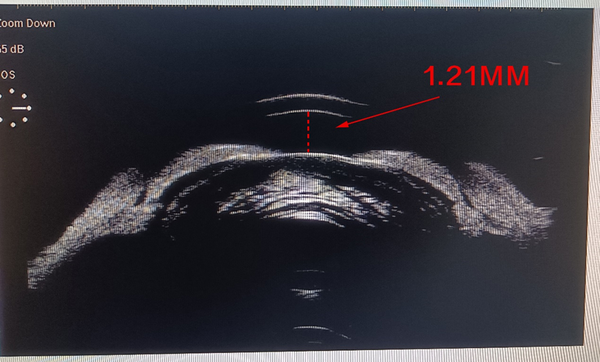

UBM检查显示,膨胀变大的晶状体挤压前房,导致房角变窄阻碍房水流通,极易导致青光眼的发生。

▲ 晶状体膨胀后的房角闭合状态

被挤压的前房深度只剩1.21mm,让晶状体和角膜的空间变得极度狭窄。手术过程中使器械操作空间受限,稍有不慎,就可能对角膜、瞳孔等造成伤害。

这些变化导致手术难度和风险呈几何级数增加。